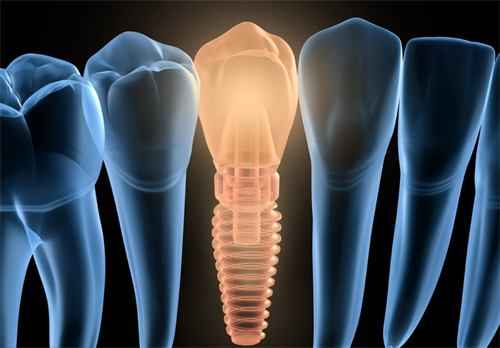

1. 种植牙项目

种植牙是修复缺失牙齿的有效方法,其费用因品牌、技术、地区差异等因素而有所不同。

1. 种植牙手术方法

种植牙手术一般包括术前检查、制定种植方案、手术植入种植体、安装愈合基台或愈合帽、安装牙冠等步骤。

在手术过程中,医生会根据顾客的具体情况选择合适的种植体和手术方法,确保手术的可行性和顾客的舒适度。